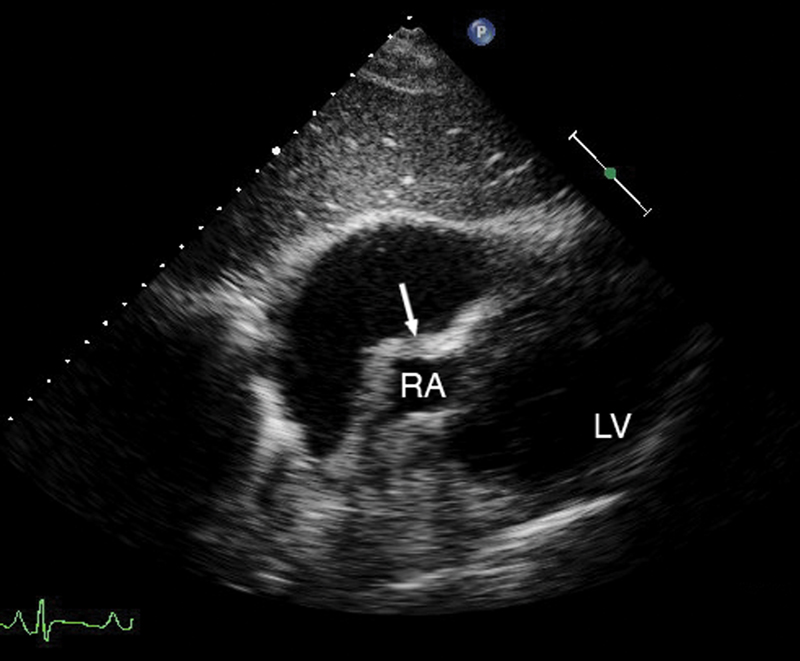

فحوصات تشخيصية لبعض امراض القلب والشرايين التاجية